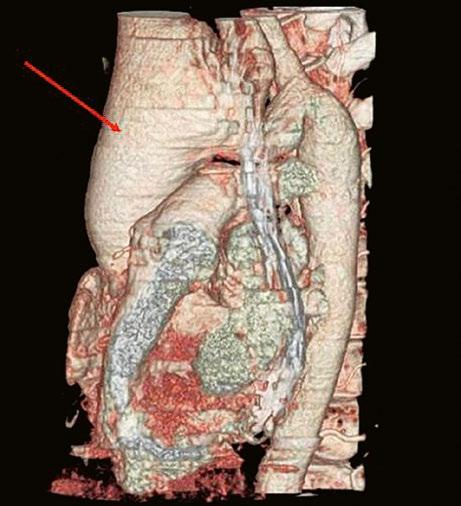

Obr. 45.11 CT angiografie, defekt typu sinus venosus superior je označen hvězdičkou, anomální pravá horní plicní žíla ústící do horní duté žíly je označena šipkou

PS – pravá síň, LS – levá síň

Obr. 45.12 CT angiografie s 3D rekonstrukcí u pacientky s defektem typu sinus venosus superior a s parciálním anomálním návratem dvou pravostranných plicních žil z horního a středního laloku do horní duté žíly, pravá dolní plicní žíla ústí normálně do levé síně